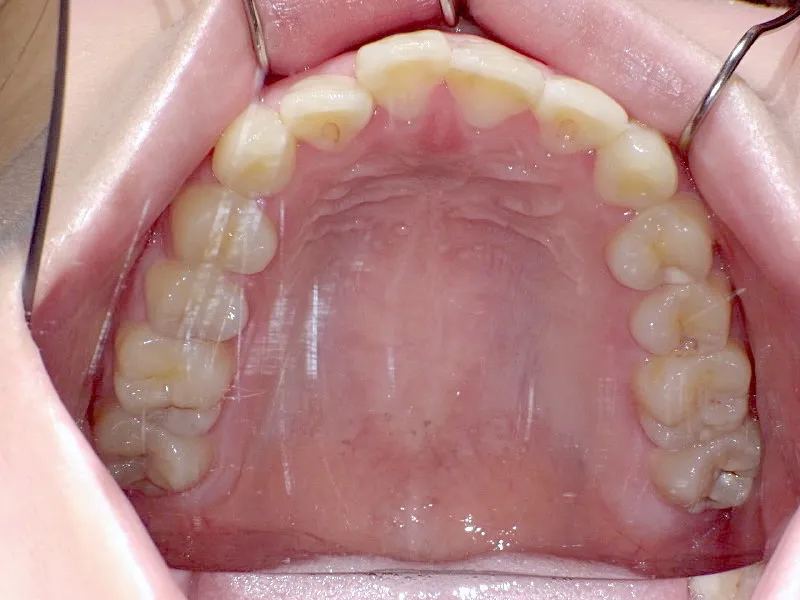

初診時

上下の歯並びがガタガタで口元が出ています。

元々小学生の時にマルチブラケット装置を上下につけ、矯正治療を受けていました。

何年か経過後、ガタガタと口元が気になると受診されました。

後戻りの原因は、リテーナーの装着時間不足、頬杖や、口呼吸などが考えられます。